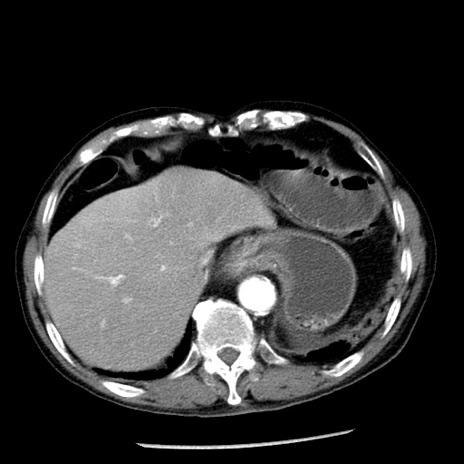

症例26(横断像)

【症例】80歳代男性

【主訴】嘔吐

【現病歴】昨晩2回嘔吐あり、今朝になっても嘔吐あり。来院。

【既往歴】胃潰瘍

【身体所見】意識清明、BT 37.6℃、BP 166/95mmHg、HR 100bpm、SpO2 97%、腹部:平坦・軟、腸蠕動音聴取良好、圧痛なし。

【データ】WBC 21900、CRP 1.46